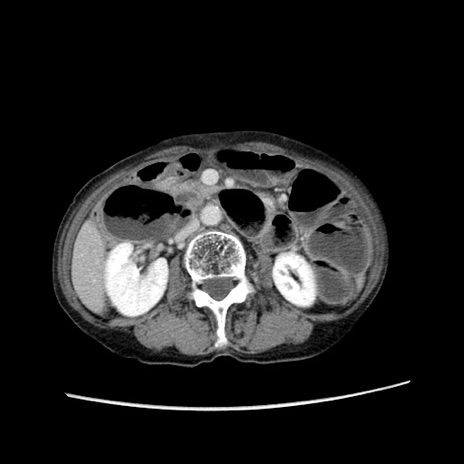

症例25(横断像)

【症例】80歳代女性

【主訴】胸のつかえ感

【現病歴】約9時間前に食後から胸のつかえた感じあり、嘔吐あり、来院。

【既往歴】胃癌(全摘)、胆摘、虫垂炎

【身体所見】心窩部に圧痛あり、反跳痛なし。

【データ】WBC 5700、CRP 0.05